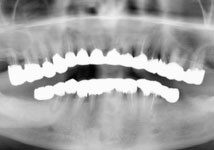

| 長年、カリエスを放置していたために、噛み合わせが悪く、食事がしにくいということで、当院を受診され、歯周再生治療と、審美補綴治療によってトータルコーディネートをしました。今は、噛み合わせも良くなり、見た目もきれいで、よく噛めると喜んでいただいております。 |